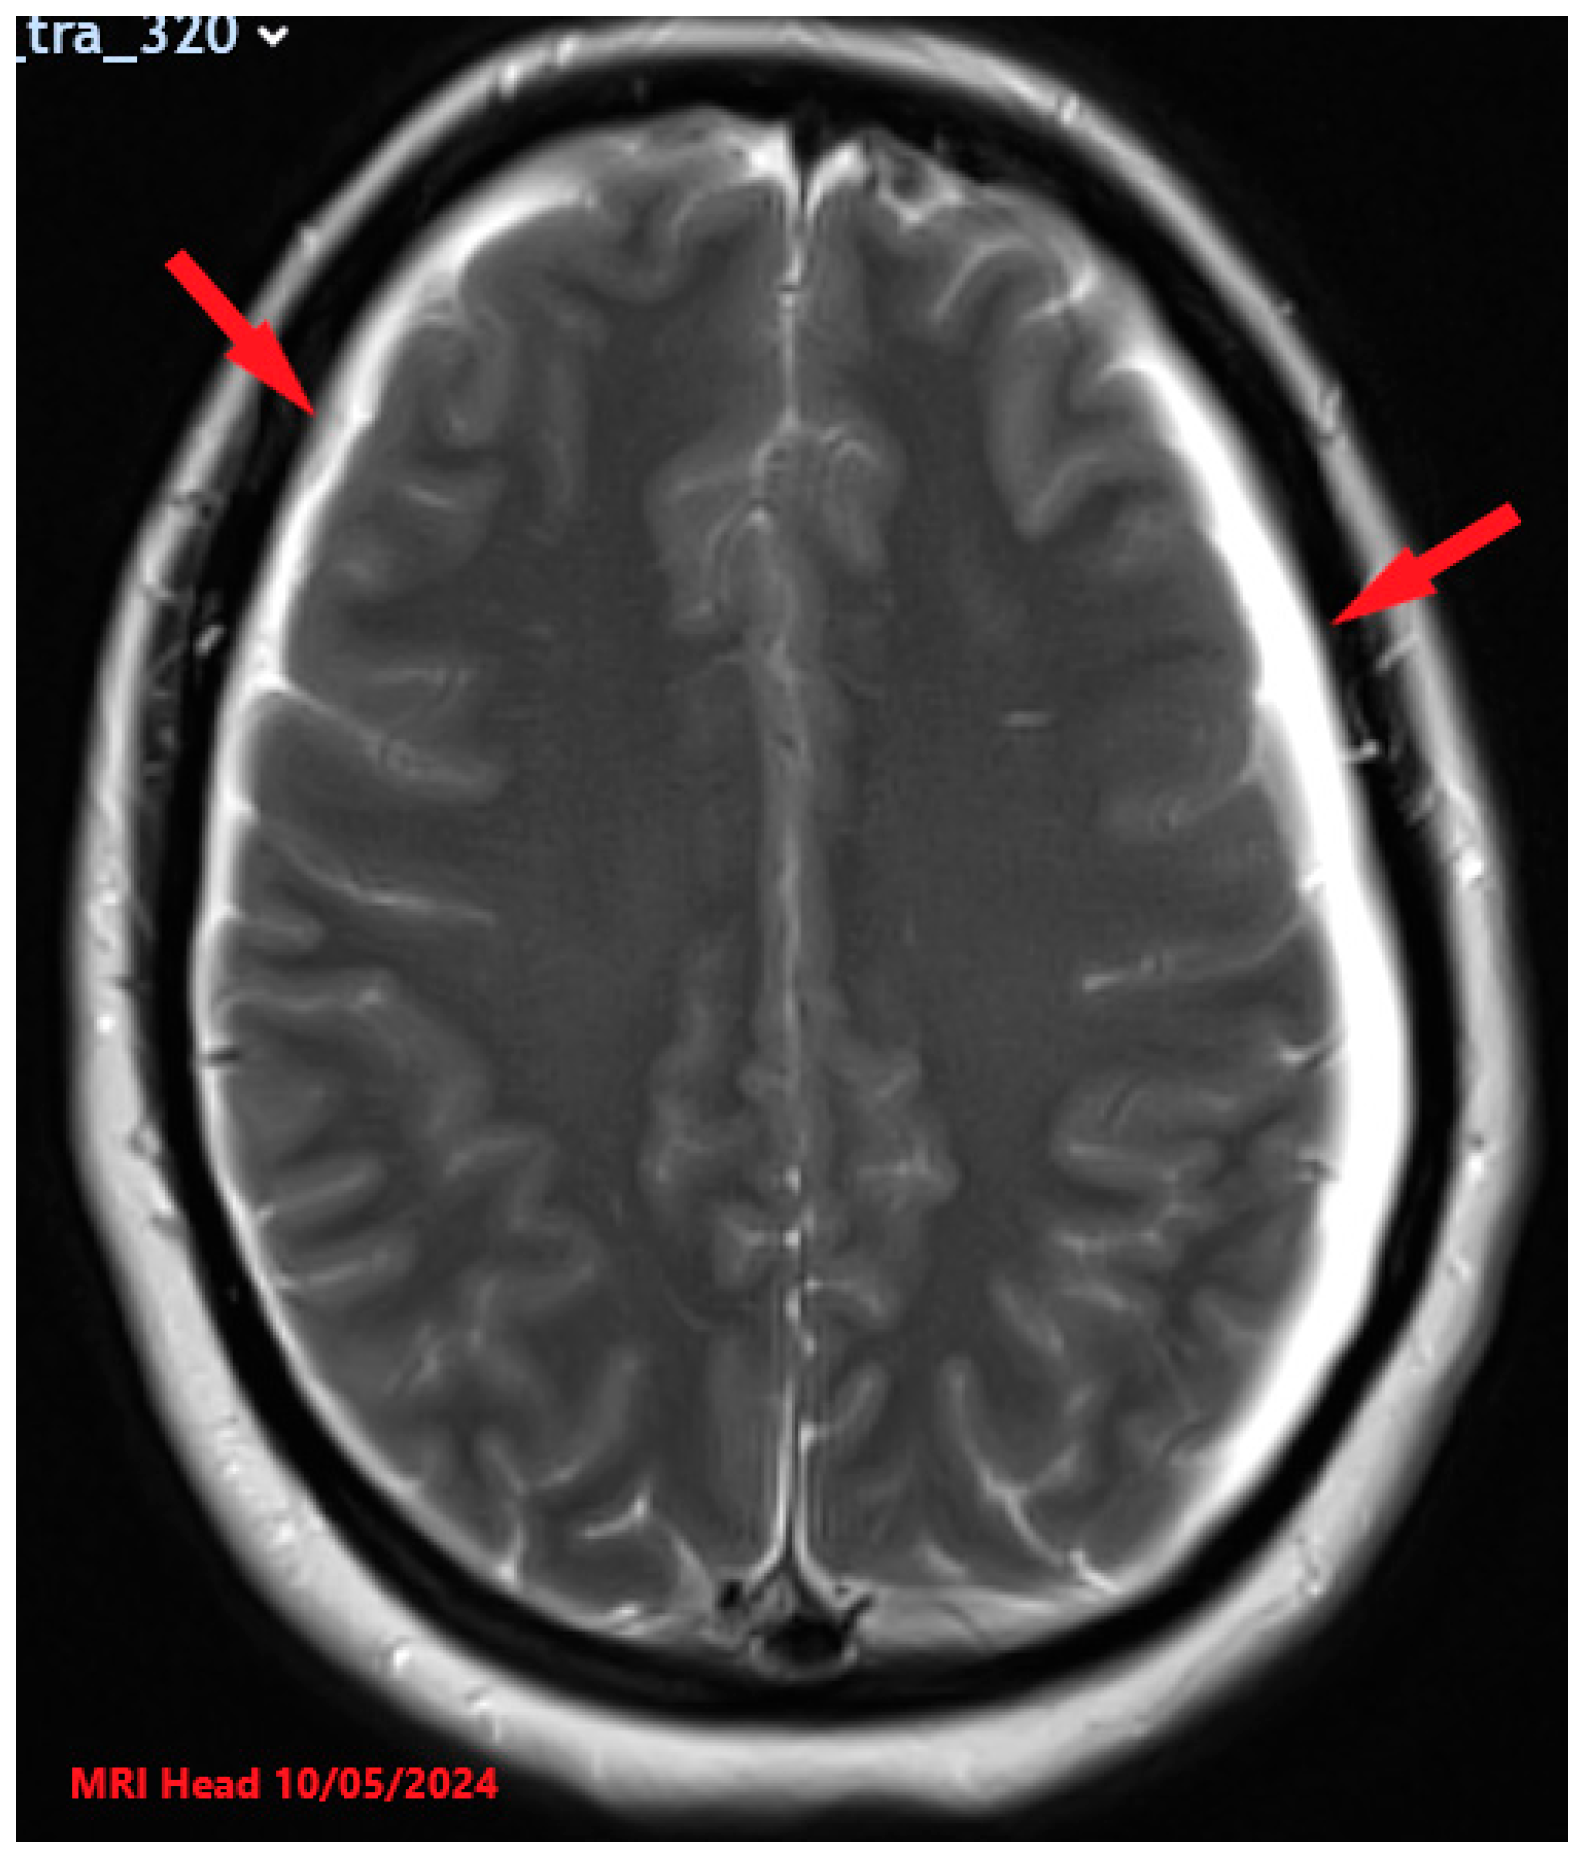

Figure 3. MRI findings (higher resolution) after the treatment showing reduction in subdural collections (red arrows). No definite demonstrable cause of the CSF leak was identified.

A follow-up MRI at 24 weeks of pregnancy revealed a reduction in cervical and lumbar spinal CSF collections, with resolution of low-pressure intracranial features (Figure 3 and Figure 4). However, a small volume of interval haemorrhage into the left subdural CSF collection was noted. She was subsequently planned for discharge with advice to maintain a headache diary, ensure adequate hydration, and balance activity and rest periods, including spending 15–20 min in an upright position every two hours. Additional recommendations included avoiding constipation, gradually weaning off analgesics, and arranging a follow-up neurological review at a tertiary centre. As she showed clinical improvement, further imaging was deemed unnecessary by the neurologists. Obstetric management included foetal echocardiography at 24 weeks due to her positive anti-Ro antibodies which are known to cause congenital heart block in the foetus. The foetal echocardiography was normal, and she received fortnightly foetal heart auscultation from 28 weeks. She had serial growth scans at 28, 32, and 36 weeks as she had risk factors for a small-for-gestational age baby. All growth scans were normal.